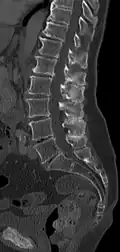

| A diagram of a human vertebral body. With Baastrup's sign, the posterior spinous process, pointing down and to the left, is abnormally thickened due to repetitive microtrauma. | |

Baastrup's sign is an orthopedic and radiographic disorder that often occurs in elderly humans. It is characterized by enlargement of the posterior spinous processes of the lumbar spine, with normal intervertebral disc height and neuroforamina. The reason it is referred to as kissing spine is because the posterior spinous processes 'kiss' and touch one another as the individual goes into lumbar extension, for example when flat on their stomach.[1][2] The condition has been seen in humans, canines, particularly with boxer breeds,[3] and certain breeds of horses.[4] This disorder is named after Christian Ingerslev Baastrup.

The salient feature of the disorder is the exuberant osteophytosis that occurs at posterior lumbar spinous processes. Osteophytes are coarse calcifications at the edges of bone that form due to repetitive stress and trauma. There is also atrophy and fatty replacement of paraspinal musculature, which can be detected by CT or MRI.[5]